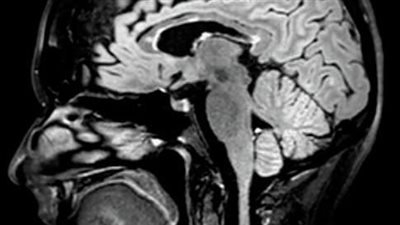

البزل الشوكى والرنين المغناطيسي يسهمان في تشخيص التصلب المتعدد

23/May/2023